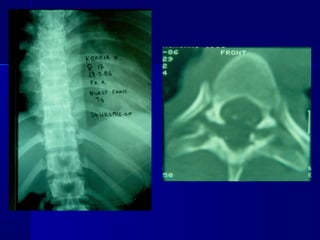

RRaaddiioollooggiiccaall

eevvaalluuaattiioonn

RRaaddiioollooggiiccaall ppaarraammeetteerrss

 KKyypphhoossiiss ooff tthhee

vveerrtteebbrraall bbooddyy

 SSeeggmmeennttaall

kkyypphhoossiiss

 DDiisscc hheeiigghhtt

 VVeerrtteebbrraall bbooddyy

hheeiigghhtt::BBeecckk iinnddeexx